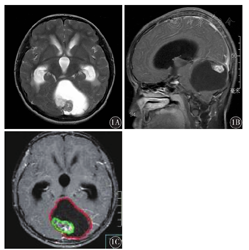

低级别组男性2例,女性7例,平均年龄7.1岁,病程3~180 d,平均45.3 d。MRI检测结果显示,病变发生于小脑5例,四脑室4例;合并梗阻性脑脊液8例;肿瘤总体积(51.1±3.2)mm3;实性成分所占比例为41.7%;合并周围脑实质水肿4例(4/9);肿瘤囊变9例(4/9)。高级别组男性6例,女性7例;平均年龄5.8岁。病程3~60 d,平均23.3 d;MRI检测结果显示,病变发生于小脑蚓部4例,四脑室6例;合并梗阻性脑脊液10例;肿瘤总体积(31.9±1.8)mm3;实性成分所占比例为66.1%;合并周围脑实质水肿4例(4/10);肿瘤囊变4例(4/10)。两组MRI影像结果比较,肿瘤总体积、实性成分所占比例差异有统计学意义(t=2.591,P=0.019;χ2=6.52,P<0.05);其余差异均无统计学意义(均P>0.05)(图1、图2)。

1A:T2WI轴位可见囊性为主巨大占位性病变,囊内有瘤;1B:增强扫描T1WI矢状位囊内肿瘤明显强化,囊性部分未强化;1C:将原始数据输入Pinnacle三维治疗计划系统,勾画出肿瘤轮廓、肿瘤实性成分区域的范围,得出肿瘤总体积80.4 mm3(红色区域),实性成分体积7.1 mm3(绿色区域);实性成分所占比例为8.9%